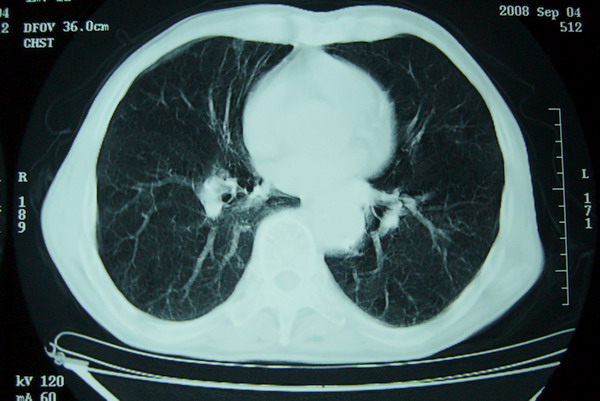

右上周围型肺癌,慢支,肺气肿。

右上肺一不规则团块,边缘有分叶和毛刺,纵隔有淋巴结肿大。右肺周围性肺癌首先考虑。